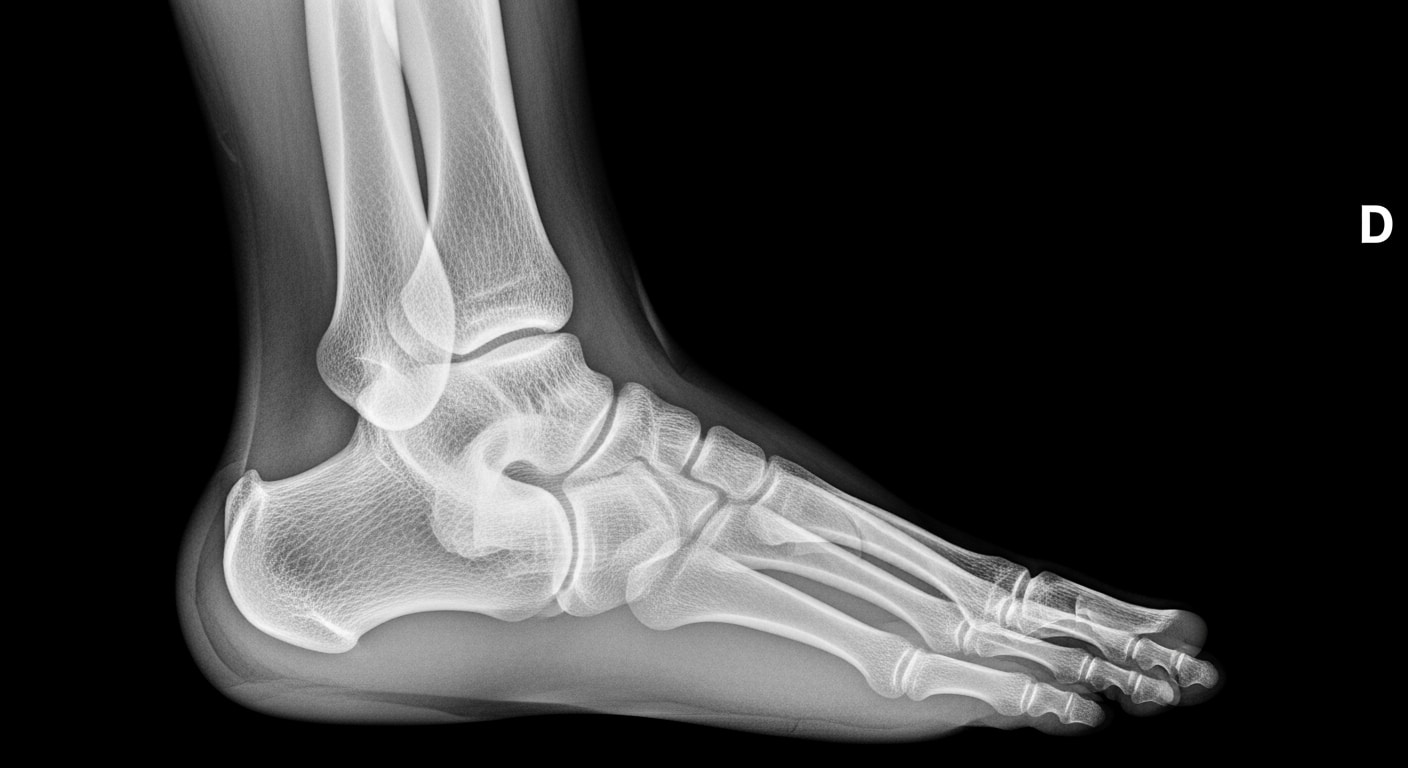

• Suspected broken bones with visible deformity, swelling, or inability to bear weight

• Joint dislocations or severe sprains with deformity

Suspected single fracture, severe sprains with deformity, workplace injuries, moderate trauma, joint dislocations. Needs x-ray evaluation within 1-2 hours at emergency facility for proper treatment planning.

The region's extensive highway system including Interstate 20 and Highway 158 contributes to motor vehicle collision rates 38% higher than state averages, leading to more emergency presentations for chest x-rays, extremity imaging, and trauma surveys[12]. Our trauma emergency capabilities include specialized protocols for multi-trauma patients requiring rapid full-body imaging assessment. Additionally, West Texas's aging population increases fall-related fracture rates by 45% among residents over 65, requiring immediate x-ray imaging to guide fracture management and prevent complications[13].

Priority ER's diagnostic capabilities for emergency x-ray services exceed Joint Commission standards for emergency departments[14], featuring digital radiography systems typically found only in major trauma centers. Our x-ray system produces images with 99% diagnostic accuracy compared to conventional film standards, enabling detection of subtle fractures, pneumothorax as small as 5%, and foreign bodies requiring surgical removal[15]. The integration of picture archiving and communication systems (PACS) allows instant image transmission to consulting orthopedic surgeons when complex fractures require specialized surgical planning.

Advanced imaging diagnostics through our comprehensive capabilities include not just standard x-ray views but also CT scanning, ultrasound, and specialized radiographic series for complex trauma evaluation. For patients with multi-system injuries, our imaging department performs trauma series protocols, dedicated spine imaging, and advanced reconstructions automatically, crucial for identifying life-threatening injuries that standard urgent care x-rays cannot fully assess. This technology gap explains why the American College of Emergency Physicians recommends freestanding ERs over urgent care for all significant trauma requiring immediate comprehensive imaging.